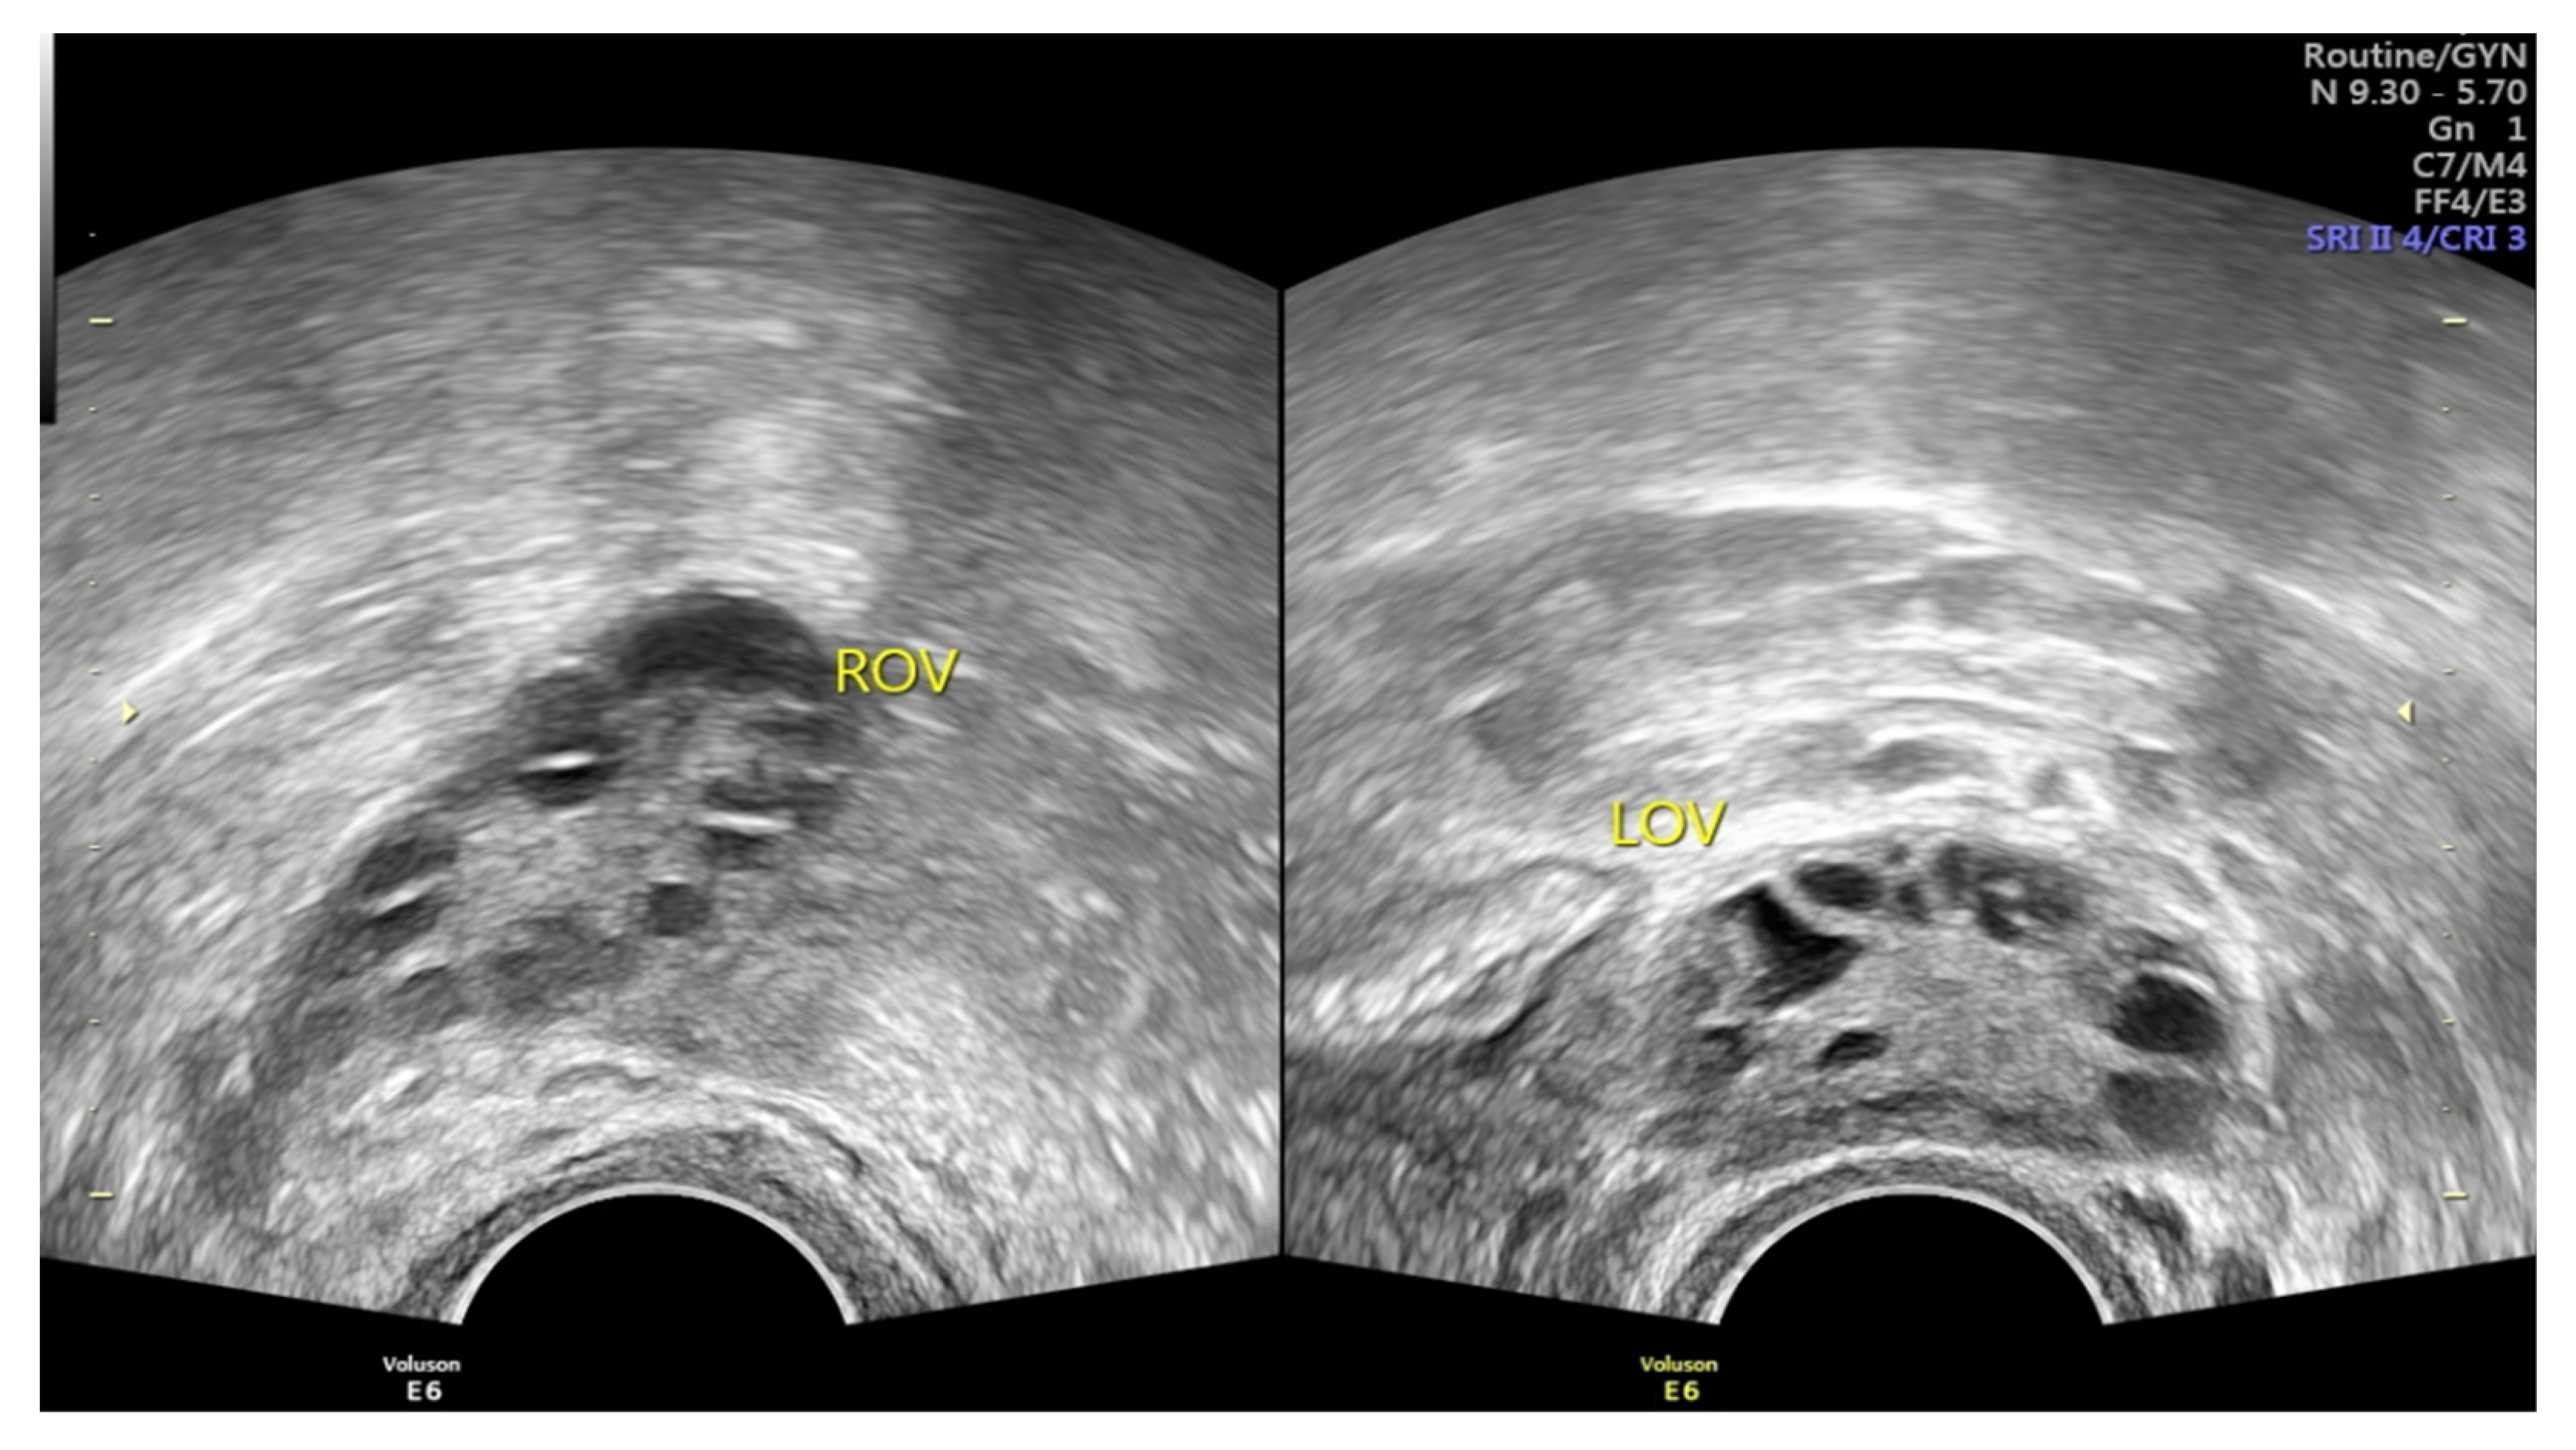

Polycystic ovary syndrome (PCOS) is the most common endocrine disorder among fertile females [1,2,3], affecting approximately 4 to 14% of reproductive-age females [1,2,3,4]. As a heterogeneous disorder of chronic anovulation, it is characterized by clinical or biochemical hyperandrogenism, ovarian dysfunction, and polycystic ovarian morphology (PCOM) according to the Rotterdam criteria [2,3,4,5,6,7,8]. Under pelvic ultrasound, PCOS is defined as the findings of multiple immature follicles and/or increased volume in bilateral ovaries [4,5] (Figure 1). More than just a reproductive syndrome, PCOS is currently viewed as a disorder with metabolic consequences which could affect women’s health during different stages of life [8]. This complicated reproductive and metabolic syndrome includes insulin resistance, menstrual irregularity, infertility, androgen excess, obesity, and a chronic low-grade inflammatory state [1,7]. It is also associated with other metabolic syndromes including dyslipidemia and increases the long-term risk of type 2 diabetes mellitus [2,9,10]. Insulin resistance is prevalent among PCOS patients, and as such the probability of type 2 diabetes is 5 to 8-fold compared with females without PCOS [10,11]. Type 2 diabetes and insulin resistance are often intertwined with PCOS; however, both of these co-morbidities seem not inevitable, and can be improved under good dietary or medical control.

Figure 1. Images of PCOS under pelvic ultrasound, showing multiple immature follicles of necklace shape and/or increased volume in bilateral ovaries (Image source: Taipei Tzu-Chi hospital, Taipei, Taiwan).